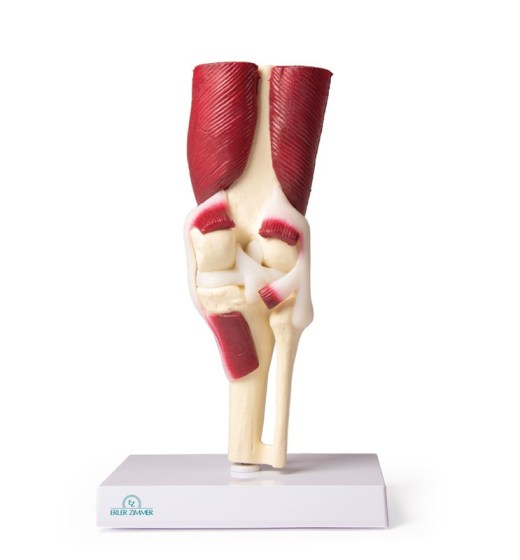

Kolenní kloub, životní velikost, se svaly

Kolenní kloub ve skutečné velikosti se všemi důležitými svaly a vazy ( kolaterální vazy, meniskus, zkřížené vazy, patelární šlacha). Kloub není pohyblivý. Popisky německy / anglicky.

Rozměry: 8 x 24 cm

Hmotnost: 0,8 kg